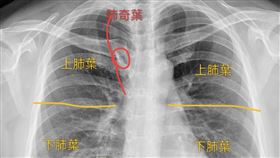

肺葉多一片!醫:像刀把肺部切出一小塊

胸腔內科醫師蘇一峰昨(2)日在臉書分享,有病人照X光...